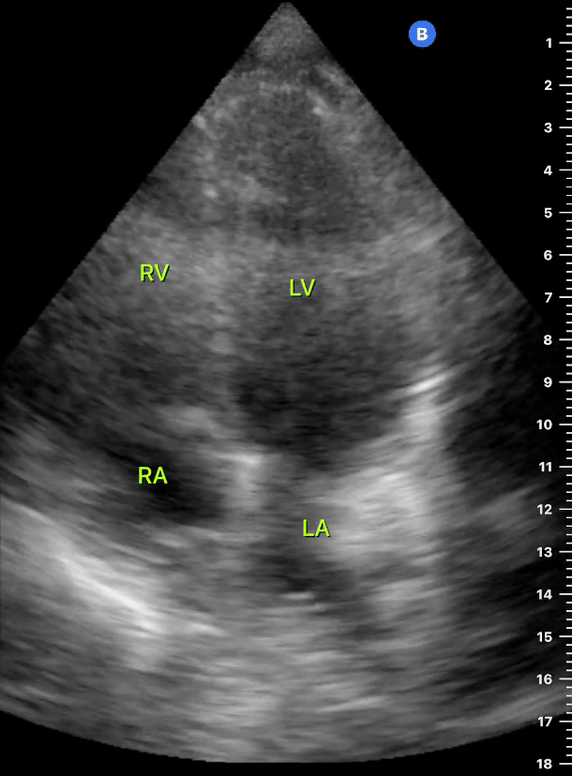

This view looks at the heart from the apex. When done properly, it achieves a horizontal cut of the heart that demonstrate all four chambers simultaneously. Consequently, its main utility is to assess the relationship between LV and RV. Beware, differentiating the chambers by ventricle size or thickness is not recommended, and it could lead to confusion in case of RV enlargement.

ORIENTATION & TECHNIQUE

Place the transducer at the apex beat and angle it towards the right scapula. The correct image results from sliding the probe until the interventricular septum is in the middle of the screen, vertically dividing both sides of the heart. If using a cardiac preset, the probe’s marker points towards the patient’s left arm. Simpler, in this view, the probe notch should meet the marking on the screen, which is fundamental to avoid confusion.